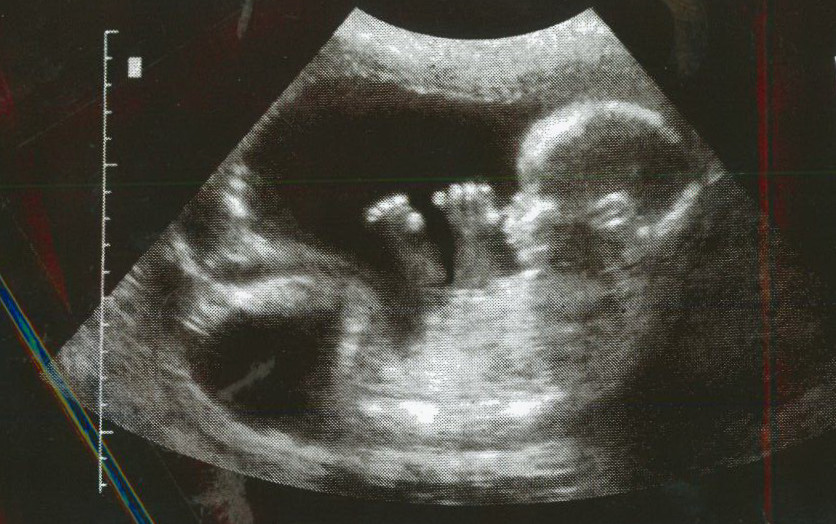

Any rational person will agree that an embryo, left alone in a mother’s womb, will grow to maturity as a human person. An embryo is not simply a group of cells that may or may not develop into a crying baby. The embryo is not just a useless glob of tissue that will amount to nothing, but rather a person who will develop into crying human baby. In other words the embryo, left alone under the usual conditions, will develop into a child that will be recognized by everyone is already a human being.

From the moment of fertilization an embryo has the ability to grow into what everyone will acknowledge to be a human person. The embryo, from the moment of fertilization, is a human embryo; it will only become a human person and not a monkey or even an oak tree. From the moment of fertilization the embryo is a being because it is whole being, that is it contains within itself all that it will need to develop into a mature child, with an existence. The embryo, while not looking like a human person, certainly exists and lacks nothing. Those who argue that an embryo does not look like a child and thus is not a child miss the point. An embryo does look like a child at birth; it looks like a child at that particular stage of development just as a new born baby does not look like he will look when he turns 80.